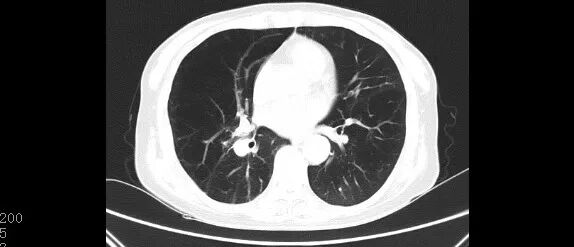

“肺大泡是不是绝对不能用无创呼吸机?”

肺大泡并不是无创呼吸机治疗的绝对禁忌症,有肺大泡又需要呼吸机治疗的患者,可以在密切观察下谨慎使用,但设置的参数要比常规设置更低,避免压力过大导致肺大泡破裂。